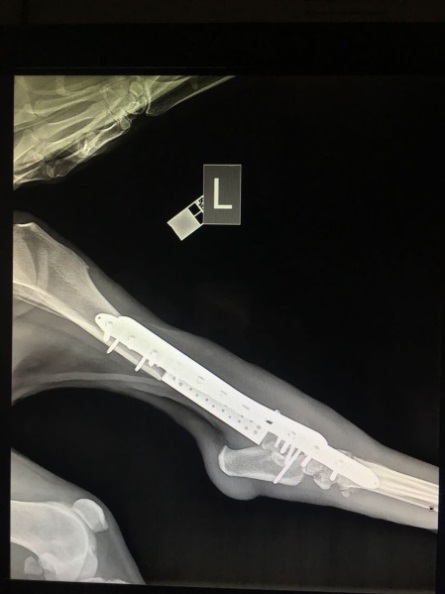

Рис. 1 — Рентгеновский снимок задней конечности животного до операции. Остеосаркомой поражено почти 11 см костной ткани.